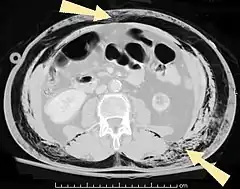

Abdominal

- Pneumoperitoneum (or peritoneal emphysema), air or gas in the abdominal cavity. The most common cause is a perforated abdominal viscus, generally a perforated peptic ulcer, although any part of the bowel may perforate from a benign ulcer, tumor or abdominal trauma.